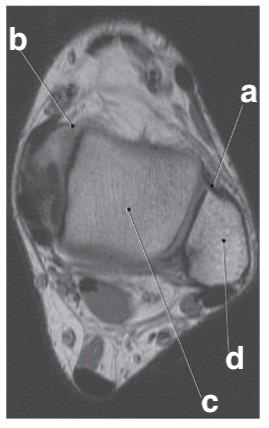

Which letter is the talus?

c

What imaging plane is this?

coronal

What is letter e?

Achilles tendon

a